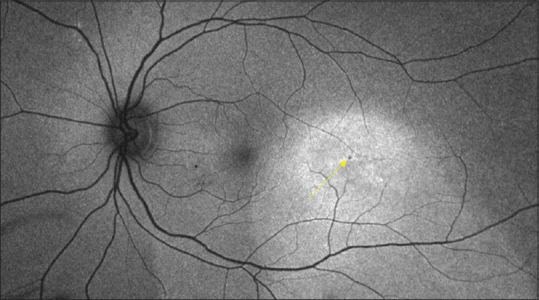

Fluorescein-free detection of focal leak in a patient with acute central serous chorioretinopathy.

Fundus fluorescein angiography (FFA) is considered the gold standard for identifying focal leaks in central serous chorioretinopathy (CSCR). However, there are situations where FFA cannot be performed, and alternative noninvasive investigations are required to pinpoint area of focal leaks. We present a case of a 36-year-old female patient with bilateral steroid induced acute CSCR with three distinct fluorescein-free signs converging in the same area indicating presence of focal leak.